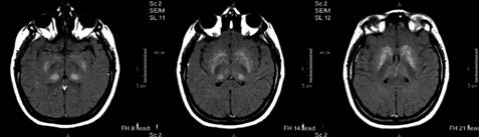

Resonancia magnética de encéfalo. Nota aclaratoria: imagen de susceptibilidad magnética, donde se evidencia la ausencia de sangrado, por lo que los hallazgos en T1, aunque son hiperintensos, no corresponden a sangrado y son compatibles con depósitos de calcio.

Figura 2: Resonancia magnética de encéfalo. Nota aclaratoria: imagen de susceptibilidad magnética, donde se evidencia la ausencia de sangrado, por lo que los hallazgos en T1, aunque son hiperintensos, no corresponden a sangrado y son compatibles con depósitos de calcio.

Fuente: elaboración propia.